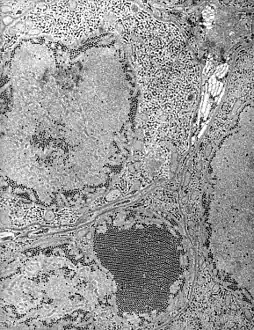

فيروس التهاب دماغ القديس لويس (بالإنجليزية: Saint Louis encephalitis virus) هو الفيروس المسبب لالتهاب دماغ القديس لويس.

الفيروس مرتبط بفيروس التهاب الدماغ الياباني فكلاهما من الفيروسات المصفرة ومن جنس الفيروسة المصفرة.